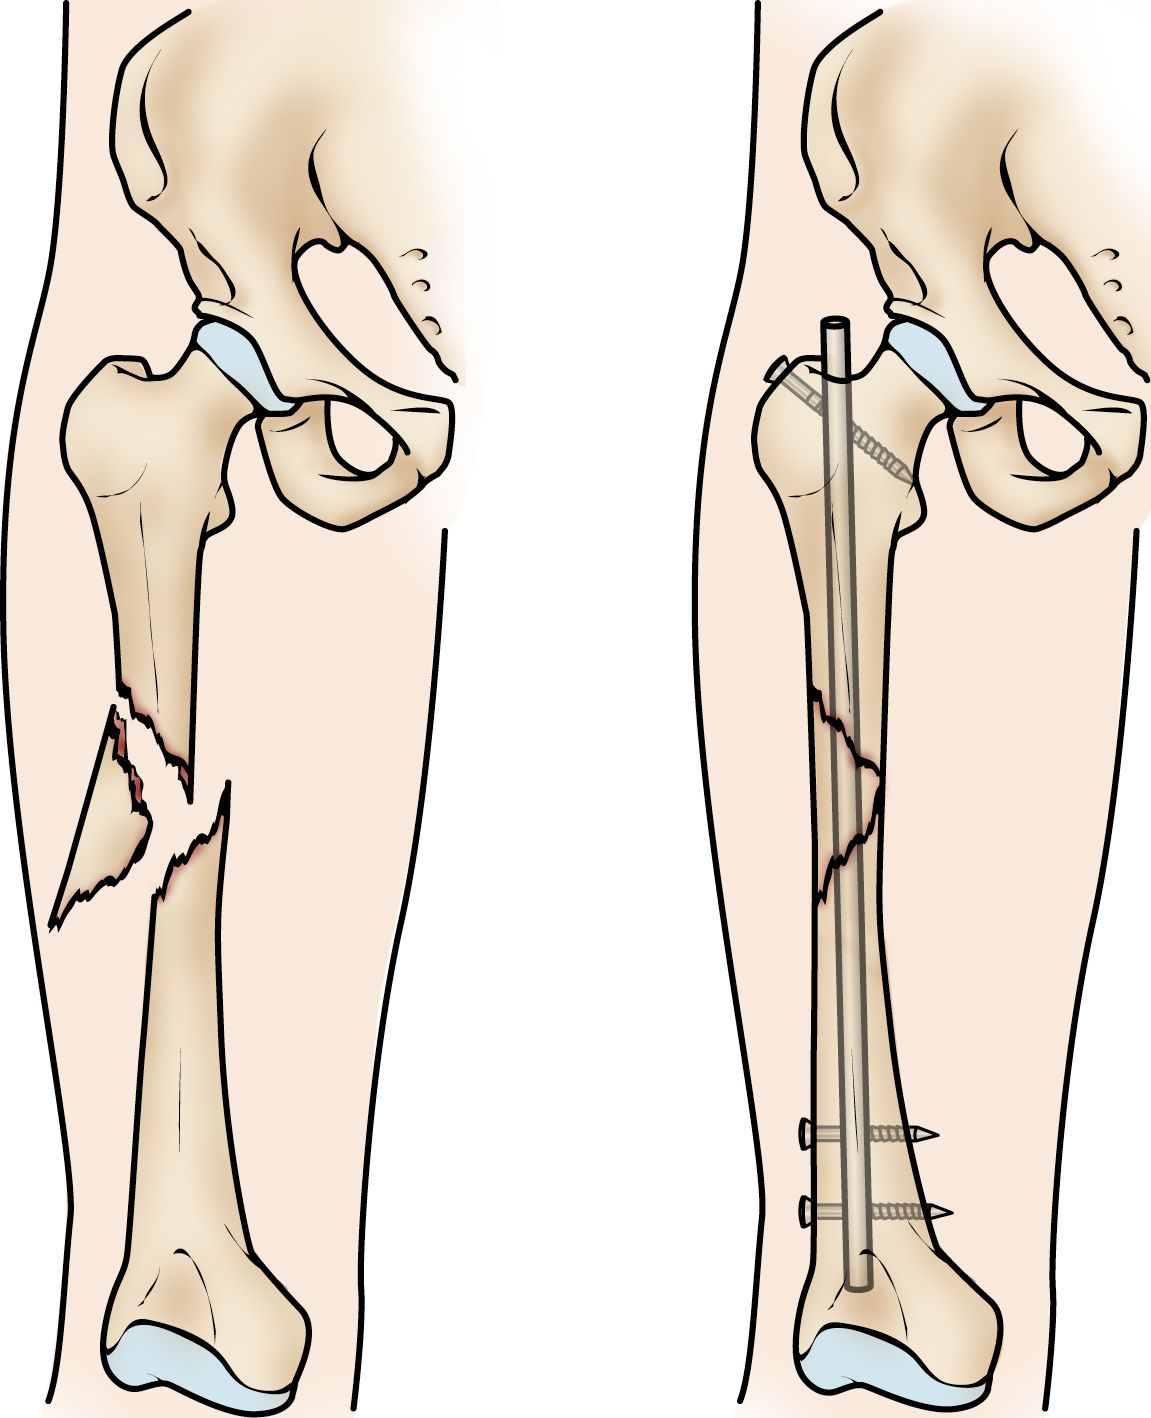

Intramedullary nailing. Currently, the method most surgeons use for treating femoral shaft fractures is intramedullary nailing. During this procedure, a specially designed metal rod (nail) is inserted into the canal of the femur. The nail passes across the fracture to keep it in position.

Intramedullary nailing of a femoral shaft fracture

Intramedullary nailing provides strong, stable, full-length fixation.

An intramedullary nail can be inserted into the canal either at the hip or the knee. Screws are placed above and below the fracture to hold the leg in correct alignment while the bone heals.

Intramedullary nails are usually made of titanium. They come in various lengths and diameters to fit most femur bones.